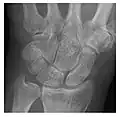

Occult osseous injuries may result from a direct blow to the bone by compressive forces of adjacent bones against one another or by traction forces during an avulsion injury. Lesions in the tibial plateau, hip, ankle, and wrist are often missed. In a tibial plateau fracture, any disruption of the posterior and anterior cortical rims of the plateau should be sought. Impaction of subchondral bone will appear as an increased sclerosis of the subchondral bone (Figure 1). In the hip, posterior acetabular fractures also present subtle radiographic findings. The acetabular lines should then be carefully examined keeping in mind that the posterior rim, which is harder to see on X-rays, is more frequently fractured than the anterior rim (Figure 2). In the wrist, detection of carpal bone fractures is often challenging, with up to 18% of scaphoid fractures radiographically occult. Carpal fractures, especially the scaphoid, are associated with the risk of avascular necrosis. In apparently normal wrist radiographs from symptomatic patients, if there is history of a fall on an outstretched hand with pain in the anatomic snuffbox, suggesting scaphoid injury, the initial examination with posteroanterior, lateral, and pronation oblique views must be complemented by other specific views such as supination oblique and the "scaphoid" view A careful examination of cortices for evidence of discontinuity or offset and cancellous bone for lucency is necessary (Figure 3).[1]

Figure 3: A 26-year-old man presenting with wrist pain after being assaulted. (a) Initial anteroposterior radiograph shows a subtle linear lucency within the scaphoid extending to the scaphocapitate articular surface that was overlooked (arrow). (b) Initial "scaphoid" view was negative. (c) Followup anteroposterior radiographs, 12 days later, shows obvious scaphoid fracture (arrows).[1]